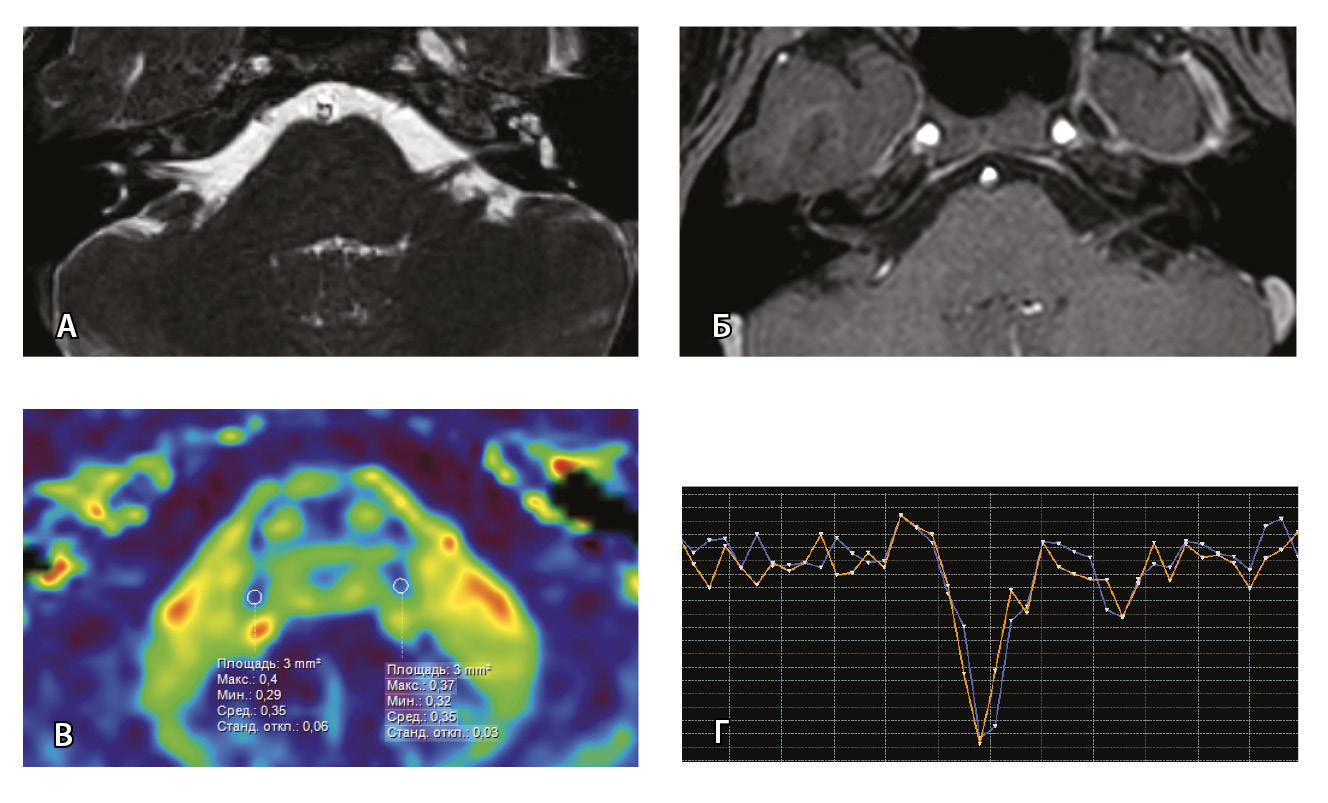

Рис. 6. Пациентка З. Магнитно-резонансная томография (МРТ) головного мозга: А – прицельная T2-SSFP на область мосто-мозжечкового угла; Б – Т1-взвешенное изображение с контрастным усилением; В – диффузионно-тензорная МРТ (фракционная анизотропия, ФА); Г – Т2*-перфузия. На изображении T2-SSFP патологические изменения на уровне прохождения лицевых нервов во внутренних слуховых проходах не определяются (А). При контрастировании отмечается накопление контрастного вещества правым лицевым нервом во внутреннем слуховом проходе (Б, красная стрелка). На уровне моторных ядер лицевого нерва в заднем отделе варолиевого моста на изображениях ФА на стороне поражения отмечается минимальное уменьшение показателя ФА до 0,33 (В, черная стрелка) и признаки гипоперфузии справа (Г, оранжевый график) по сравнению с контралатеральной стороной (Г, синий график). Данный пример демонстрирует типичные изменения при мультипараметрической МРТ у пациента с параличом Белла